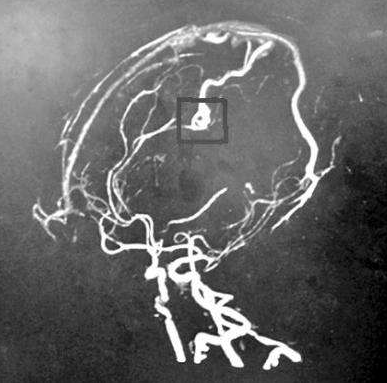

脑海绵状血管瘤无症状或者偶然发现,需要手术吗?脑海绵状血管瘤常会因非特异性或无关症状而做影像学检查时被发现(图1)。对于无症状的脑干海绵状血管瘤和单次发作并没有导致严...